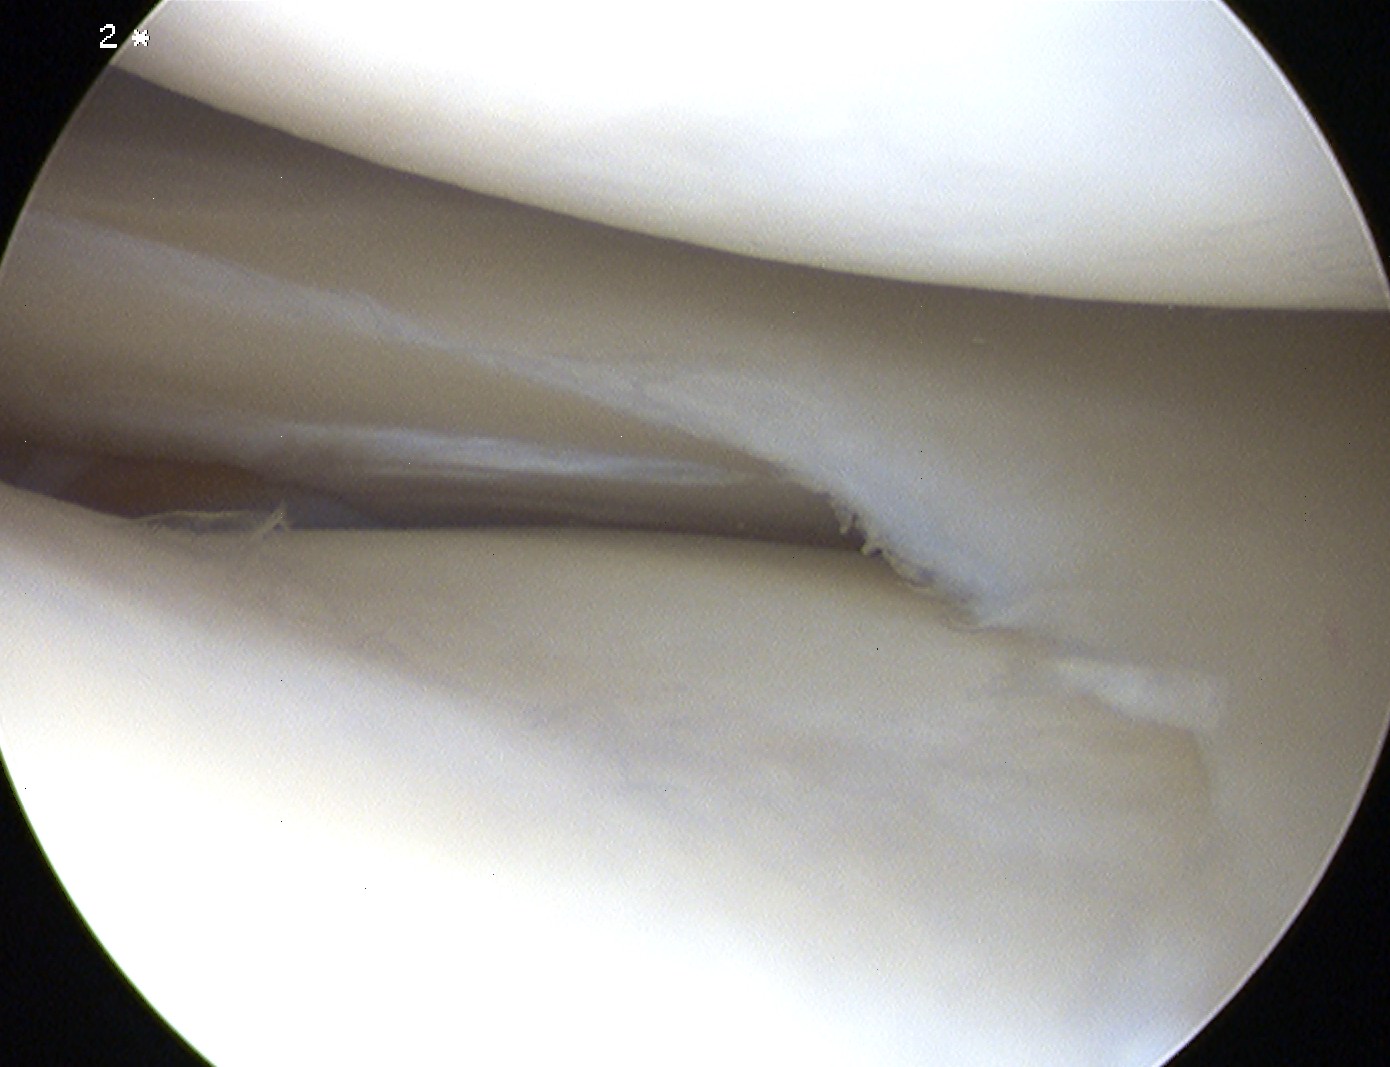

3. Oblique

Vertically oriented full-thickness tear

- runs obliquely from inner edge of meniscus out to body of meniscus

- if base posterior, referred to as posterior oblique tear & vice versa

4. Radial

Vertically oriented full thickness tear

- extends from inner edge radially to periphery

Incomplete

- doesn't extend to periphery

Complete

- extends to periphery

Parrot beak tear

- incomplete radial tear with anterior or posterior extension